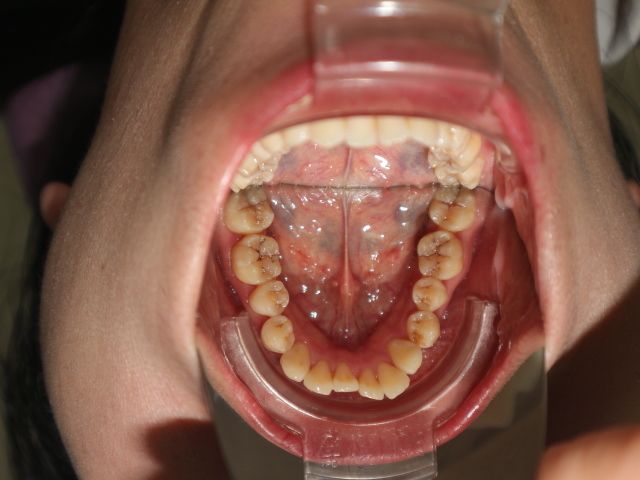

Nên niềng mắc cài hay invisalign cho tình trạng răng khấp khểnh vùng răng cửa, hô ở mức trung bình

Xin chào các bác sỹ Em đã đi tư vấn, các nha khoa đều đưa ra 2 lựa chọn mắc cài hoặc invisalign. Vậy em xin hỏi với trường hợp của em, phương pháp nào tối ưu, hiệu quả, tiết kiệm thời gian và an toàn hơn? Em cảm ơn.

Có thể khắc phục được tình trạng răng chen chúc xô lệch mà không cần nhổ răng không?

Tôi 23 tuổi và đang cân nhắc đến việc niềng răng để khắc phục tình trạng răng mọc khấp khểnh. Tôi đã đến gặp hai bác sĩ nha khoa thẩm mỹ và họ đều nói là cần phải nhổ răng nhưng tôi lại không muốn vậy. Hàm dưới của tôi gần như hoàn hảo nhưng tôi có tật nghiến răng vào ban đêm. Vậy tôi muốn hỏi là có thật sự cần phải nhổ răng hay không?